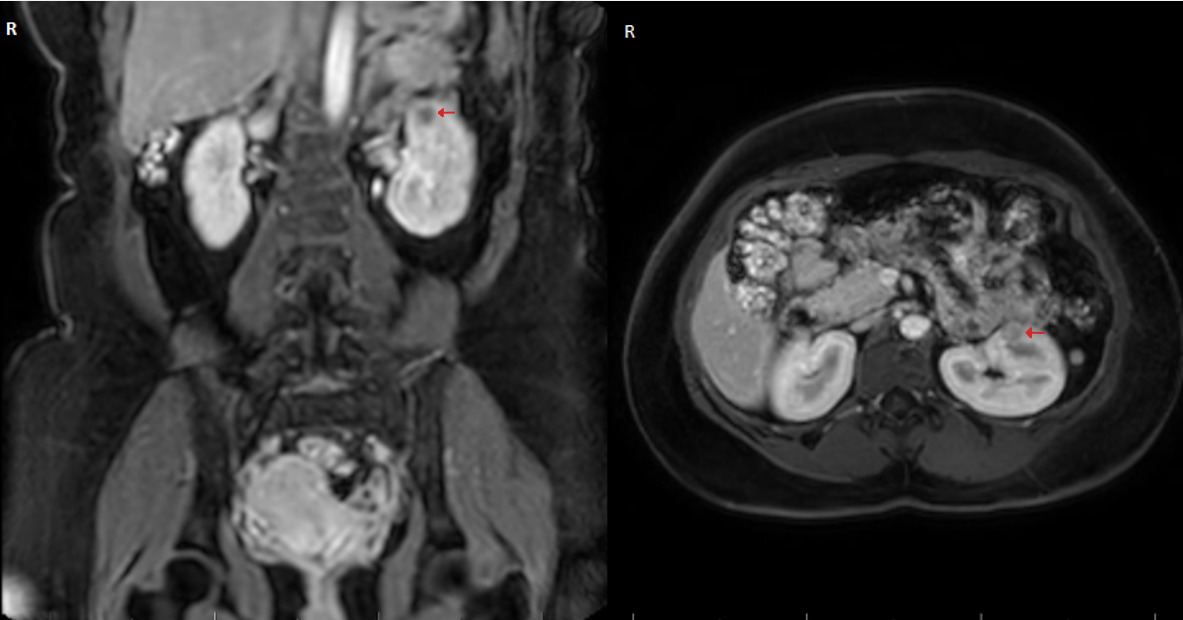

A 32-year-old woman was referred by her general practitioner to our urology department for the surgical removal of a small renal mass. Her medical history was remarkable for hypertension first diagnosed at 22 years of age, which was medically well controlled with amlodipine and enalapril. The patient reported that during the diagnostic workup of her hypertension, an elevated renin and aldosterone serum level had been noted, although the exact values could not be retrieved as the tests were performed in a different country. An external magnetic resonance imaging (MRI) in 2019 revealed a small renal mass of 8x9 mm in size in her left kidney, which was followed up with a second MRI in November 2022, revealing an increase in size to 16x13 mm and suspicion of malignancy (Figure 1). Hematuria or flank pain were denied, as was urinary discomfort or an increase in urinary frequency. Her medical history for previous abdominal surgeries or allergies was void. The physical exam revealed a soft abdomen without a palpable mass. The laboratory findings demonstrated adequate renal function with a serum creatinine of 57 µmol/l and a glomerular filtration rate (Cockroft-Gault) of 118 ml/min/1.73 m2. In the perioperative screening potassium levels were normal. According to the patient hypokalemia was also absent in previous blood tests.